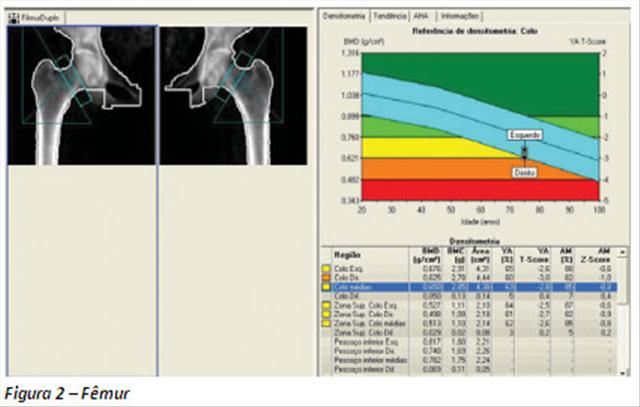

O método realiza medidas quantitativas da massa óssea em certos locais do corpo humano. No geral, as partes de interesse na obtenção das imagens para diagnóstico são o fêmur e a coluna vertebral, tendo em vista que as partes do corpo mais afetadas na osteoporose são: o colo do fêmur, a coluna, a pelve e o punho.